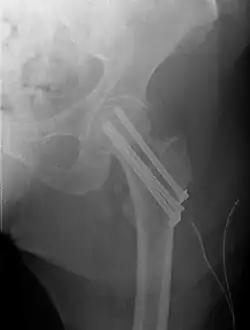

Trochanteric fracture

A trochanteric fracture, below the neck of the femur, has a good chance of healing.

Closed reduction may not be satisfactory and open reduction then becomes necessary.[43] The use of open reduction has been reported as 8-13% among pertrochanteric fractures, and 52% among intertrochanteric fractures.[44] Both intertrochanteric and pertrochanteric fractures may be treated by a dynamic hip screw and plate, or an intramedullary rod.[43]

The fracture typically takes 3–6 months to heal. As it is only common in elderly, removal of the dynamic hip screw is usually not recommended to avoid unnecessary risk of second operation and the increased risk of re-fracture after implant removal. The most common cause for hip fractures in the elderly is osteoporosis; if this is the case, treatment of the osteoporosis can well reduce the risk of further fracture. Only young patients tend to consider having it removed; the implant may function as a stress riser, increasing the risk of a break if another accident occurs.